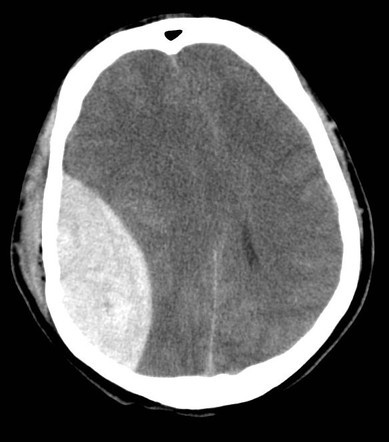

SUSPECT diagnosis - Hx, deep coma, deteriorating GCS, pupillary dilatation.

INVESTIGATE - CT